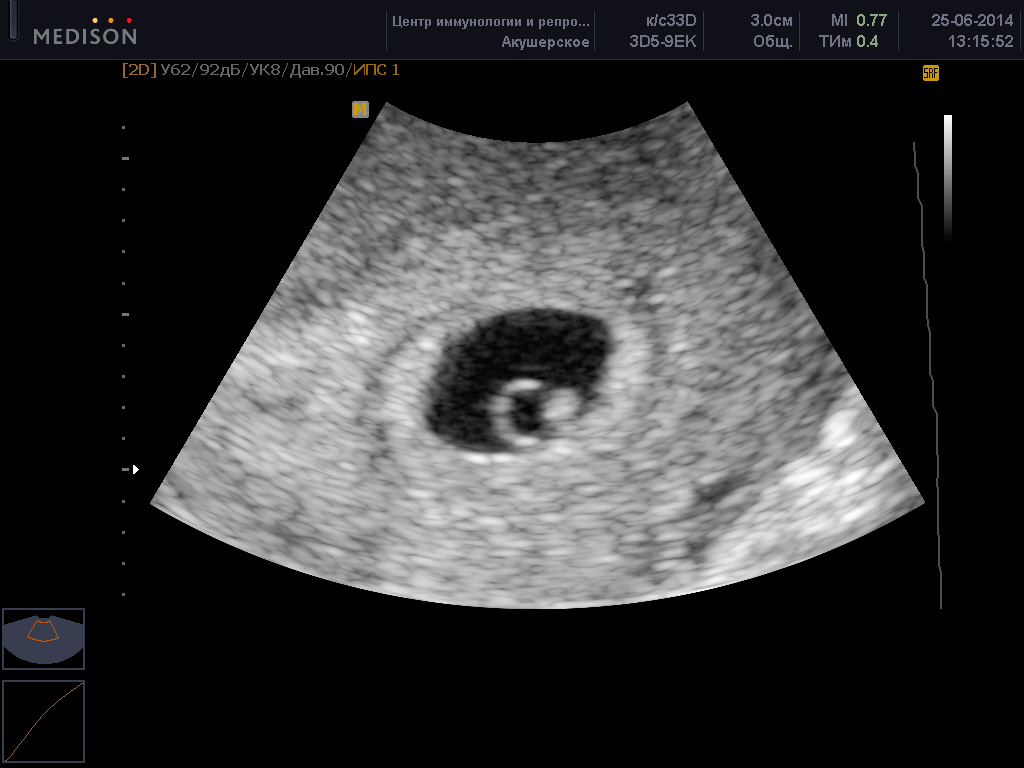

Важно: обязательно посещать все плановые скрининговые УЗИ и своевременно проходить назначенные обследования!